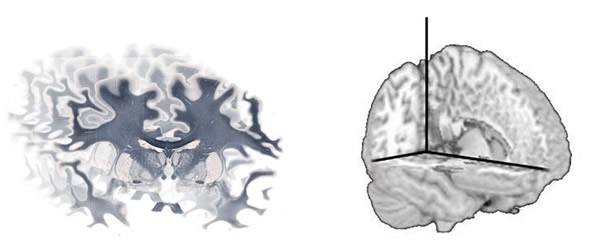

In addition, TissueScope™ can be used to acquire z-stacks and optical sections on specific ranges of tissue up to 500μm or even 2mm in depth using the appropriate clearing methods. Use of the optional TissueSnap™ workflow accessory avoids the need for pre-processing and preview scanning, meaning the main scanner can operate at full throughput and the time to view is further reduced. The scans performed using a Huron scanner are stored in non-proprietary, open .tiff format, which enables researchers to use a range of image analysis software to create 3D reconstructions of tissue (Figure 2).

A series of whole brain images can be reconstructed using software to produce a 3D volume.

Picture 2. A series of whole brain images can be reconstructed using software to produce a 3D volume. Image credit: Huron Digital Pathology.